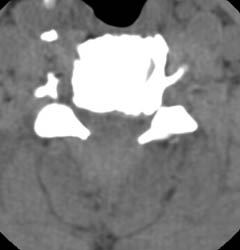

63 y.o. male with severe spinal stenosis and associate myelopathy in both hands and feet. Patient underwent laminectomy from C2-C7. 1 day after initial operation patient with severe numbness to left arm. Then, patient became unable to move either leg within 2 hours after that initial complaint. A Stat non-contrast CT was ordered.

Axial CT demonstrates laminectomy defect at the level shown. A hyperdense fluid collection with some air bubbles  is identified consistent with an epidural hematoma, extending from the C2-3 level to C7-T1 (not entirely shown).